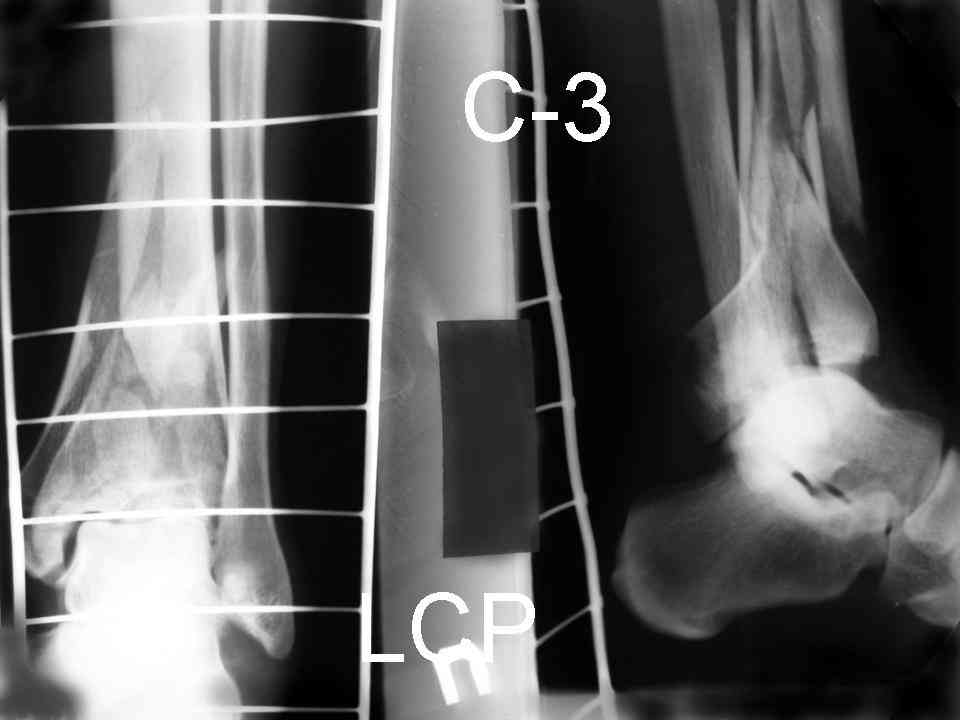

На рентгенограммах типичный перелом пилона по типу С-3. есть опыт до 100 открытых опреаций у нас в клинике. 20 примерно в год. Принцип один -все внутрисуставные переломы нуждаются в открытой репозиции и внутренней стабильной фиксации. При поступлении КТ не надо, так как получается только нагромождение костей. Истинной картины нет. Главное восстановить длину малоберцовой кости - это ключ к успеху. При поступлении меньше всего надо думать о сосудистых расстройствах, т.к. сама операция и репозиция даже сначала частичная даёт улучшение сосудитых нарушений. Причём очень быстро. Операция в 2этапа. При поступлении доступ позади наружной лодыжки, причём обязательно. После этого репозиция малоберцовой кости и фиксация пластиной 1/3 трубки под винт 3,5. Дренаж и любой аппарат наружной фиксации. Затем после спадения отёка на 5-7-10 день аппрат снимается и дугообразный разрез спереди от медиальной лодыжки 10-12 см. Главной чтобы расстояние между 1 и вторым разрезом было не меньше 7-8 см. Тогда не будет некрозов лоскутов. Таранная кость используется как матрица на неё укладываются отломки и фиксируются пицами. Ренг-контроль. Отломки лежат все отдельно, но ничего не высыпется. При переломах С-3 всегда нужна костная пластика (из крыла). Фиксация пластиной лист клевера простой или LCP. Гипс не нужен. Дренаж до 48 часов. Операция длится 3-4 часа обязательно без жгута. Посылаю примерно такой же случай.

Посылаю результат лечения предыдущего больного через год.

С уважением Дрягин